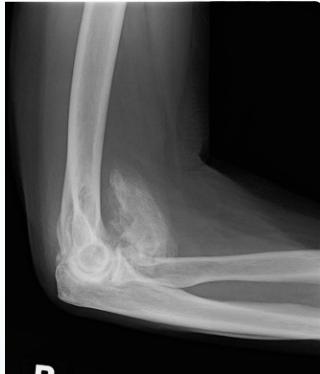

- Pathological fracture: minor trauma / strange fracture line

Soft Tissue and Traumatic Conditions

- Soft tissue hamartomas

- Myositis ossificans

- Stress fracture:

- Histopathology may be confused with osteosarcoma?

- Tendon avulsion injuries:

- Near hip and knee (e.g. Osgood-Schlatter)